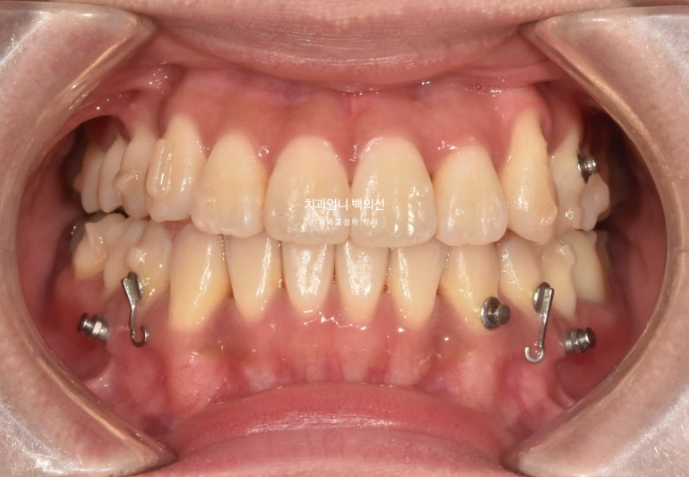

25.03

25년 1월부터 25년 3월까지 장치를 모두 낀 후 모습입니다.

총 치료기간은 1년 6개월입니다.

드디어 완벽히 일치하는 치아 중심선과 안정적인 덧니 배열

치아중심선은 위 아래 치아끼리 맞는 것도 중요하지만, 전반적인 인중과 얼굴과도 맞아야 합니다.

어금니 교합이 좋지 않으면 치료를 마무리 짓지 않습니다.

23.09~25.03

초진 3mm의 중심선 불일치가 해결되었습니다.

윗니가 아랫니를 덮는 양이 안정적입니다.

잘 내려와준 덧니입니다.

앞니가 거꾸로 물리던 부분도 정상교합을 찾았습니다